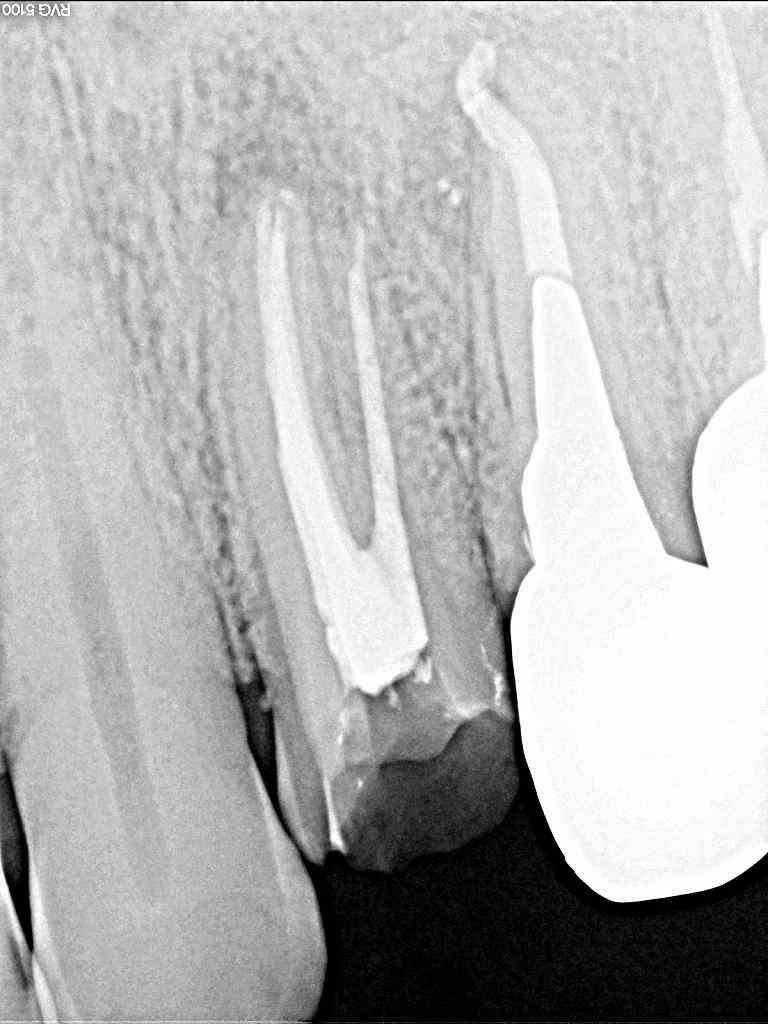

根の治療の問題があって噛むと痛むとのこと 左上4,5番の根の治療|お知らせ |広島市安佐南区の歯科医院 根の治療の問題があって噛むと痛むとのこと 左上4,5番の根の治療 トップ お知らせ・ブログ お知らせ 根の治療の問題があって噛むと痛むとのこと 左上4,5番の根の治療 根の治療の問題があって噛むと痛むとのこと 左上4,5番の根の治療 このような被せがはいいています 根元が痛いとのこと 4,5番に根の病気がありました 5番より治療していきました 2本治療してありました、、 2根幹が治療してありました 腫れてきたりしました 3根管ありました 珍しいですga, 3根管ありました 綺麗に治療できましたので、治るかと思います Web診療予約 初めての方へ 選ばれ続ける理由 院内設備について 歯が痛いしみる一般歯科 歯がぐらぐらする歯周病 健康な歯を保ちたい予防歯科 子供の虫歯予防をしたい小児歯科 銀歯をセラミックに審美歯科 白い歯を目指しませんか?ホワイトニング 矯正専門医がいるので安心矯正歯科 抜けた歯を補いたいインプラント・入れ歯 医院案内 スタッフ紹介 メリィハウス歯科クリニックオフィシャルホームページ ラベンダー歯科クリニックオフィシャルホームページ お知らせ・ブログ ホーム 診療科目 一般歯科 歯周病治療 予防治療 小児歯科 審美治療 ホワイトニング 矯正歯科 入れ歯・インプラント マウスピース矯正 初めての方へ 院長・スタッフ 設備紹介 医院案内・アクセス メニューを閉じる